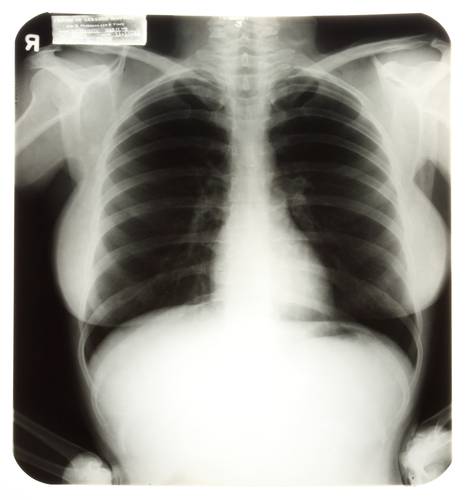

Los Ángeles, 28 de junio. Tres radiografías del pecho y la pelvis de la actriz Marilyn Monroe, tomadas durante un chequeo médico, se vendieron por 45 mil dólares, más de 10 veces el valor estimado antes de la venta.

Las radiografías de Monroe fueron tomadas durante una visita al hospital Cedros de Líbano, en Los Ángeles, en 1954. La actriz falleció en agosto de 1962, a los 36 años.